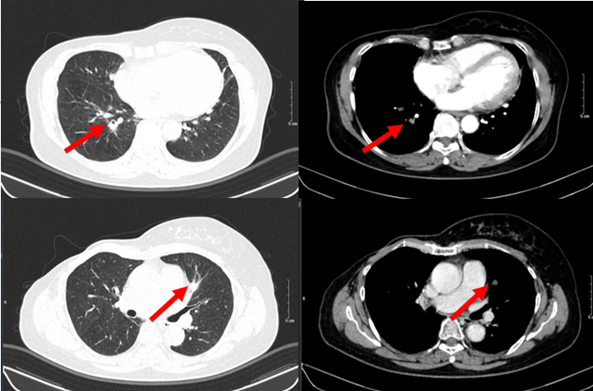

Hình 2. Hình ảnh chụp CT ngực trước điều trị: Tổn thương phổi 2 bên

Hình 8. Hình ảnh chụp CT ngực trước và sau điều trị: Tổn thương phổi trái

Hình 9. Hình ảnh chụp CT ngực trước và sau điều trị: Tổn thương phổi phải

– Chụp cắt lớp vi tính ngực:

+ Phổi phải: nhu mô thuỳ giữa và dưới có các khối – nốt đặc, lớn nhất 7x8mm

+ Phổi trái: nhu mô thuỳ trên và đáy phổi sát màng phổi có các khối nốt đặc, lớn nhất 9x8mm